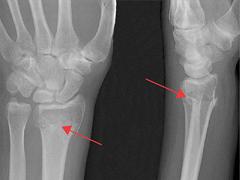

De distale radiusfractuur Lees meer over De distale radiusfractuur De distale radiusfractuur

De distale radiusfractuur is een veelvoorkomende fractuur die meestal ontstaat door een val op de uitgestrekte hand. Voor dit type fractuur worden verschillende classificatiesystemen gebruikt, maar in de literatuur is geen consensus over welk systeem gebruikt dient te worden. Op basis van de ernst van de fractuur en patiëntkarakteristieken zal de behandelend arts kiezen voor een conservatieve dan wel operatieve behandeling. Het is van groot belang dat de patiënt al vroeg in het revalidatietraject goed wordt begeleid door een fysiotherapeut. De revalidatie is in te delen in verschillende fasen: in eerste instantie ligt het accent op het verbeteren van de mobiliteit, in een latere fase steeds meer op het opbouwen van de belastbaarheid. Tijdens de nabehandeling is het belangrijk om eventuele complicaties te herkennen, zodat hiervoor een gerichte interventie kan worden toegepast.